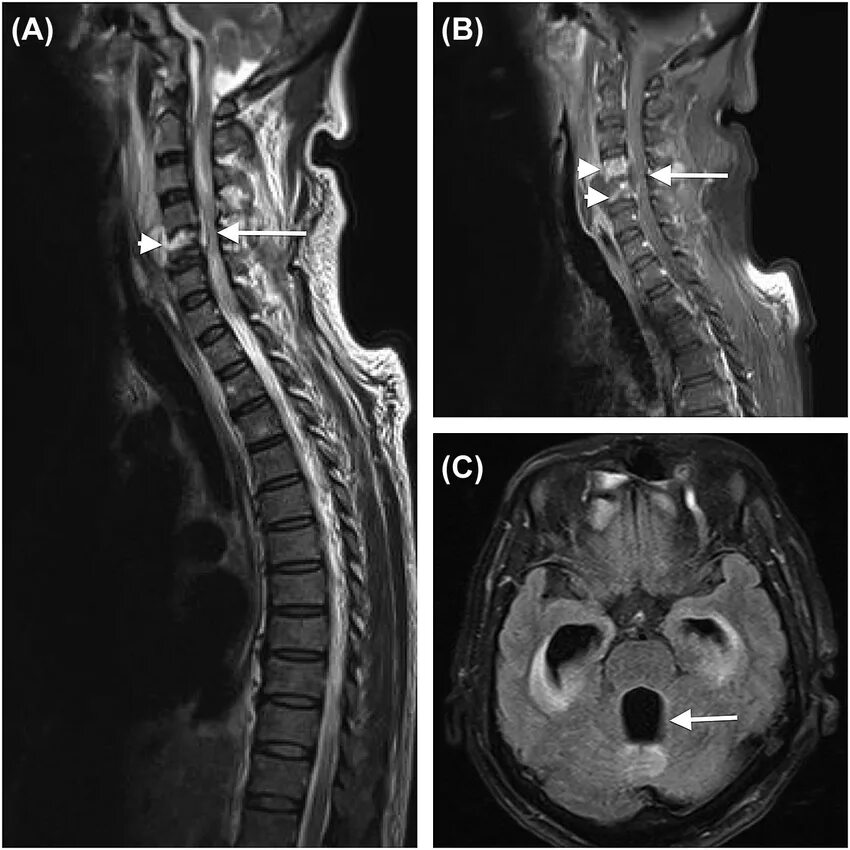

Spine mri